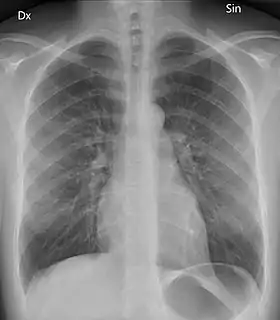

A normal posteroanterior (PA) chest radiograph of someone without any signs of injury. Dx and Sin stand for "right" and "left" respectively.

A chest radiograph, chest X-ray (CXR), or chest film is a projection radiograph of the chest used to diagnose conditions affecting the chest, its contents, and nearby structures. Chest radiographs are the most common film taken in medicine.